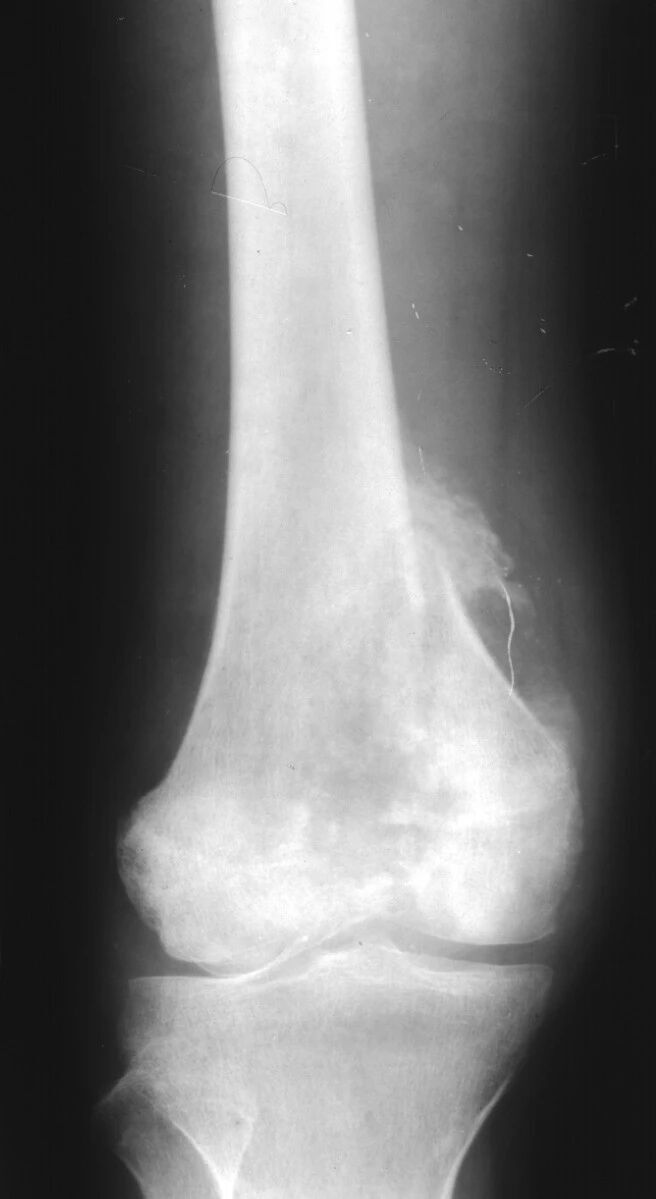

浸润性骨破坏(图 9、图 10、图 11)是肿瘤组织沿哈弗氏管呈浸润性生长侵蚀骨与骨髓的结果。往往是分化很差、高度间变、异型性明显的肿瘤组织对骨的侵蚀。影像学表现为筛孔样、虫蚀样(皮质骨)、渗透样、斑片状(松质骨)和大片溶骨性破坏,其破坏特点是肿瘤边缘模糊,境界不清,与正常骨无明显界限且有融合成片的倾向。这种不同形态的骨破坏主要是肿瘤对骨侵蚀的程度和部位不同所决定的,不能作为肿瘤定性诊断的依据。

图片

图 9.浸润性破坏:骨肉瘤